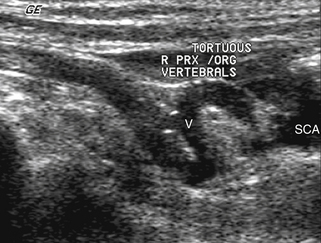

Нарушения гемодинамики кровотока в позвоночной артерии, вызванные стенотическими поражениями, можно легко обнаружить по характеристикам спектральной допплерографии и данным скорости потока. Немногие доступные исследования распространенности и естественного течения атеросклеротического стеноза позвоночной артерии показывают, что подавляющее большинство этих поражений, более 90%, возникают в самом начале. 16 Видимое сужение при исследовании цветового потока, сопровождающееся высокоскоростным смешением цветов и мозаичным рисунком, характерным для постстенотического нарушения потока, являются признаками, указывающими на стеноз позвоночной артерии. Подтверждающим доказательством является высокоскоростной поток, документированный с помощью спектральных доплеровских измерений. Не существует скоростных критериев для определения тяжести стенозов позвоночных артерий; однако увеличение скорости более чем в два раза подразумевает уменьшение диаметра более чем на 50%. Ультразвуковая диагностика стеноза в месте отхождения позвоночной артерии осложняется частым возникновением значительной извитости проксимальных 1–2 см позвоночной артерии ( рис. 11-6 ). Из-за извилистости в нестенозированной проксимальной позвоночной артерии обычно наблюдается нарушение кровотока, и может произойти перекручивание сосуда, приводящее к увеличению скорости кровотока. Извилистость также может сделать ненадежными измерения доплеровской скорости с поправкой на угол. Учитывая эти проблемы, ультразвуковую оценку происхождения стенозов позвоночных артерий следует считать качественной. Если затухающие сигналы потока присутствуют дистальнее стеноза, то можно быть достаточно уверенным, что поражение является гемодинамически значимым. В противном случае результаты часто следует рассматривать как свидетельствующие о гемодинамической значимости, и подтверждение необходимо искать с помощью ангиографии. Правильный диагноз важен, поскольку современные хирургические и интервенционные методы позволили с хорошим успехом устранить большинство стенозов проксимальных позвоночных артерий.

РИСУНОК 11-6. Продольное полутоновое изображение места отхождения нормальной позвоночной артерии. Обратите внимание на извилистость проксимального сегмента (область V1) артерии. PRX/ORG – отхождение и проксимальные сегменты позвоночной артерии.